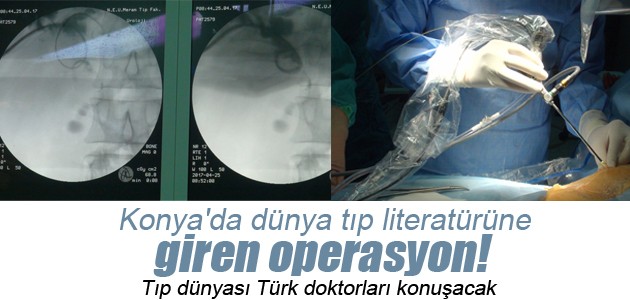

Tetkiklerde karaciğerinde 3 santimetre çapında taş olduğu tespit edilen Esen'e, müdahale için hastane doktorları harekete geçti.

Hastanenin Cerrahi Tıp Bilimleri Üroloji Anabilim Dalı Öğretim Üyesi Prof. Dr. Ahmet Öztürk, Genel Cerrahi Anabilim Dalı Öğretim Üyesi Prof. Dr. Metin Belviranlı, Girişimsel Radyoloji Uzmanı Yrd. Doç. Dr. Süleyman Bakdık ve üroloji doktorlarından Yrd. Doç. Dr. Mehmet Giray Sönmez'den oluşan ekip, ultra mini cihazlarla karaciğere müdahale ederek taşları temizledi.

Operasyonu gerçekleştiren ekipten Prof. Dr. Ahmet Öztürk, yaptığı açıklamada, ameliyatı ekip çalışması sayesinde başarıyla gerçekleştirdiklerini söyledi.

Genel bir değerlendirme sonrası açık ameliyattan ziyade endoskopik yöntemlerle taşın kırılması gerektiği fikrinin oluştuğunu aktaran Öztürk, karaciğerde irili, ufaklı taşlar olduğu için ameliyatın neredeyse imkansız olduğuna işaret etti.

Endoskopik yöntemle karaciğer içerisindeki safra kanalına girerek taşların parçalandığını, bir kısmının dışarıya ve bağırsağa itilerek müdahalenin tamamlandığını anlatan Öztürk, şöyle devam etti:

"Karaciğer çok kanamalı bir organ. Kanallar küçük. Buradaki işlemler tahribata neden olabilir. Bizim kullandığımız aletlerle kanallarda rahat hareket edip, taşa ulaştık. Kanama ihtimalini en az düzeye indirdik. Ameliyattan sonra açılan delik daha çabuk kapandı. 'Ultra mini' diyebileceğimiz yaklaşık 2,6 (8F) milimetrelik aletleri kullanarak müdahaleyi yaptık. Yurt dışında daha kalın, yaklaşık 1 santimetreye yakın aletlerle yapılmış ender uygulamalar var. Biz ultra mini dediğimiz aletlerle bu işi dünyada ilk yapan klinik olmanın gururunu yaşıyoruz. Şu anda ameliyat görüntülerini hazırlıyoruz. Uluslararası camiaya bunu duyuracağız. Video sunumlarla uluslararası toplantılarda uygulamayı anlatacağız. Endoskopik taş tedavisi tecrübemizi karaciğerdeki taşa uyguladık. Sonuçta hastamızın da bizim de yüzümüz güldü. Hepimiz mutluyuz."

- "Yöntem bu tür hastaların tedavisinde umut olacak"

Bir hastalık için tarama kanallarına girildiğinde 10 bin, 100 bin, 1 milyon yayın bulunabileceğine dikkati çeken Öztürk,"Bu şekilde bir tedavi için arama yaptığımızda 70-80 yayın karşımıza çıkıyor. Bunların içerisinde de Seyit Esen gibi vaka sayısı 2-3 yayına düşüyor. Çok az ve büyük aletlerle yapılmış. İlk olarak gerçekleştirdiğimiz ultra mini yöntem, bu tür hastaların tedavisinde umut olacak." diye konuştu.

Necmettin Erbakan Üniversitesi Meram Tıp Fakültesi Hastanesi Cerrahi Tıp Bilimleri Üroloji Anabilim Dalı Öğretim Üyesi Prof. Dr. Ahmet Öztürk (sağ 2), Genel Cerrahi Anabilim Dalı Öğretim Üyesi Prof. Dr. Metin Belviranlı (solda) ve üroloji doktorlarından Yrd. Doç. Dr. Mehmet Giray Sönmez'den (sağda)